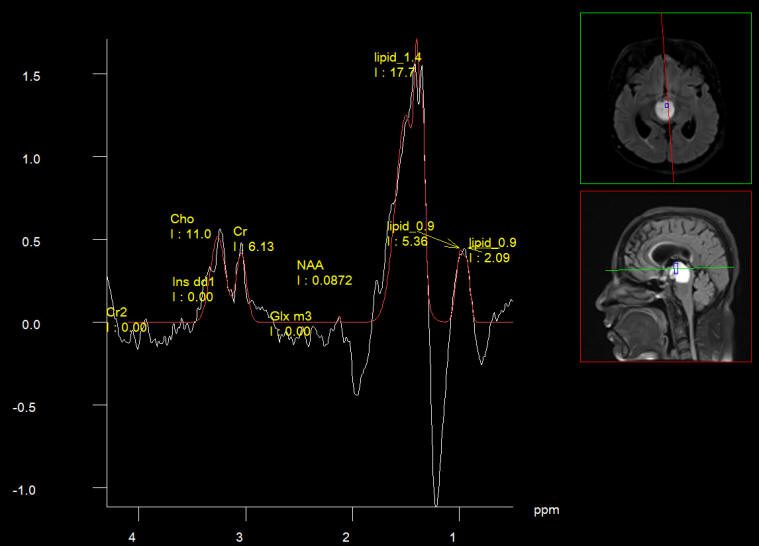

The cyst is full of lipids. It resemble thick olive oil.

Low choline, but has nidus with relative high choline.

The NAA is low and almost absent in most areas of the cyst.